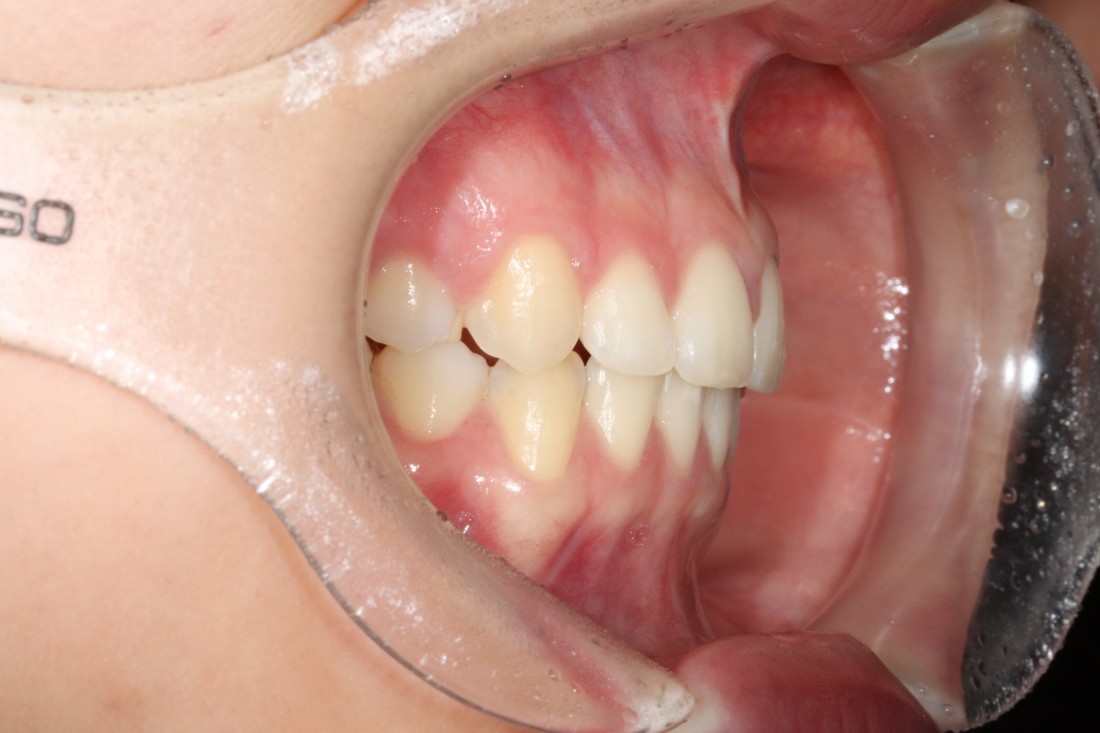

광주 교정치과는

200케이스 넘는 교정사례를

상세하게 공유해드리고 있기 때문에

실력을 믿고 맡기셔도 좋습니다.

더 다양한 교정 전/후 사례는

위의 사진을 클릭하시면

확인하실 수 있습니다.